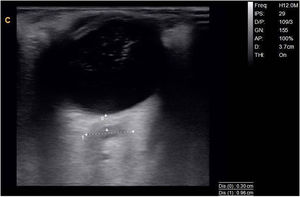

Given the diagnostic suspicion of rapidly progressive dementia with gait alterations, and the ultrasound findings suggesting intracranial hypertension, we requested an emergency brain MRI study (Fig. 2).

The study detected extensive subdural haematoma and intracranial hypertension, and the patient was referred to the neurosurgery department, where he underwent emergency craniectomy and haematoma evacuation. At 48 hours, the patient’s cognitive status had improved, with recovery of verbal episodic memory (7/8 on the Memory Impairment Screen) and orientation in time (4/5 on the MMSE subtest). Gait had improved, particularly in terms of stability, and the patient was able to walk short distances (10 m) unaided.